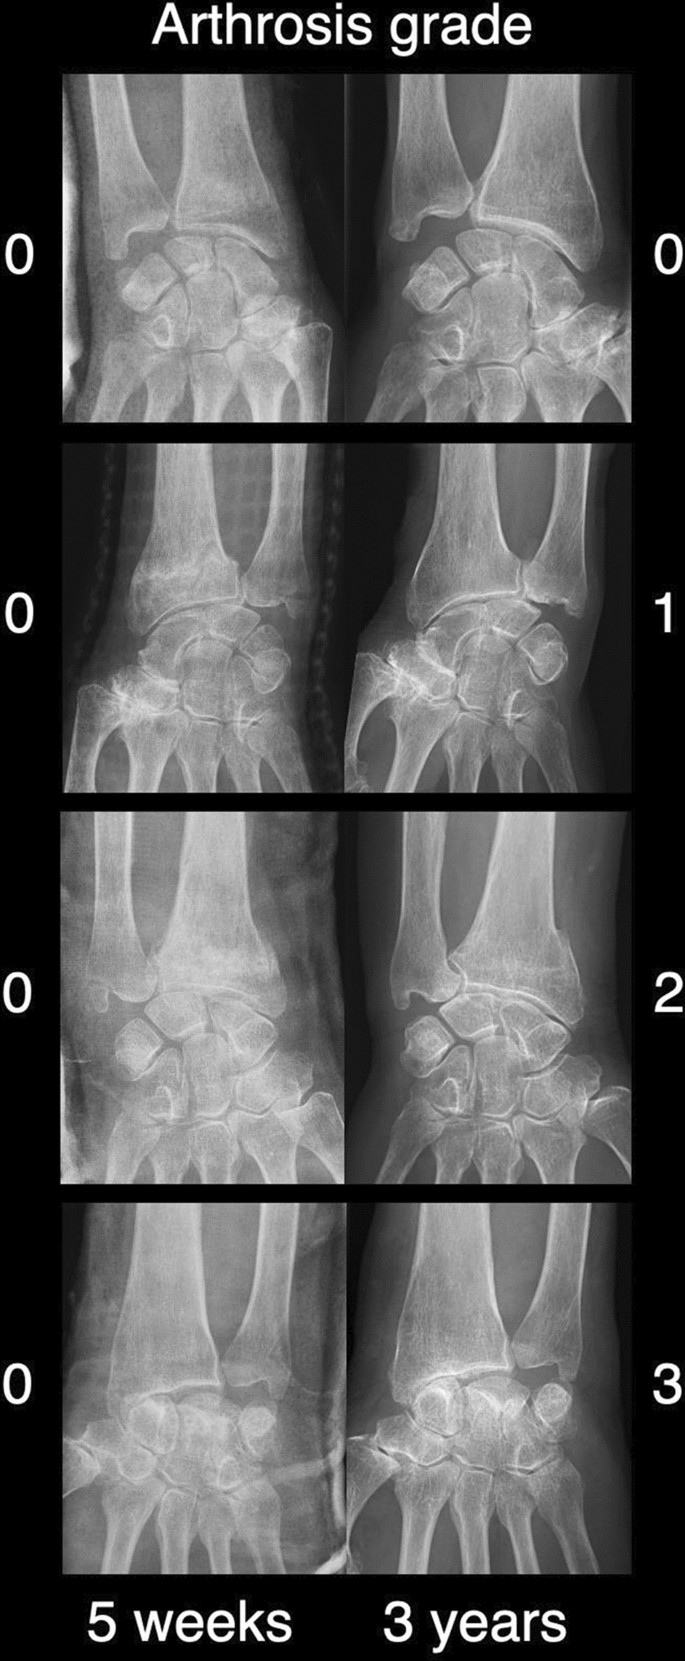

PA was the primary outcome. Standardized radiographs in two projections (anterior–posterior and lateral) were assessed by two consultants, one trauma surgeon and one hand surgeon. PA was rated according to Knirk and Jupiter15, where 0 equaled “none”, 1 equaled “slight joint space narrowing”, 2 equaled “marked joint space narrowing”, and 3 equaled “bone on bone contact”6.

The change in PA was assessed over time, i.e., radiographs taken 5 weeks after the fracture and the latest radiographs with a minimum of 3 years of follow-up.

In total, 10 out of 32 wrists had signs of PA after a mean follow-up time of 3.3 years (95% CI: 3.1–3.4; min. 3.0; max. 4.1). Arthritis was not evident in any of the 32 wrists 5 weeks post-injury (Fig. 2). At the latest follow-up, 7 wrists were rated as PA grade 1, 2 as PA grade 2, and 1 as PA grade 3. This change was statistically significant, i.e., 0/32 patients after 5 weeks and 10/32 patients after 3 years had radiological signs of wrist arthritis (Fisher’s exact test, p < 0.001). For details and the association between PA and pain please refer to Table 2.